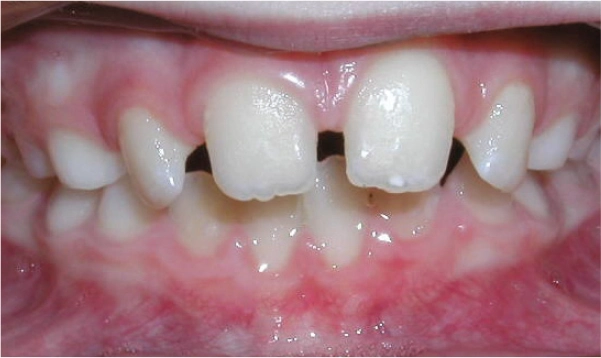

Diastema